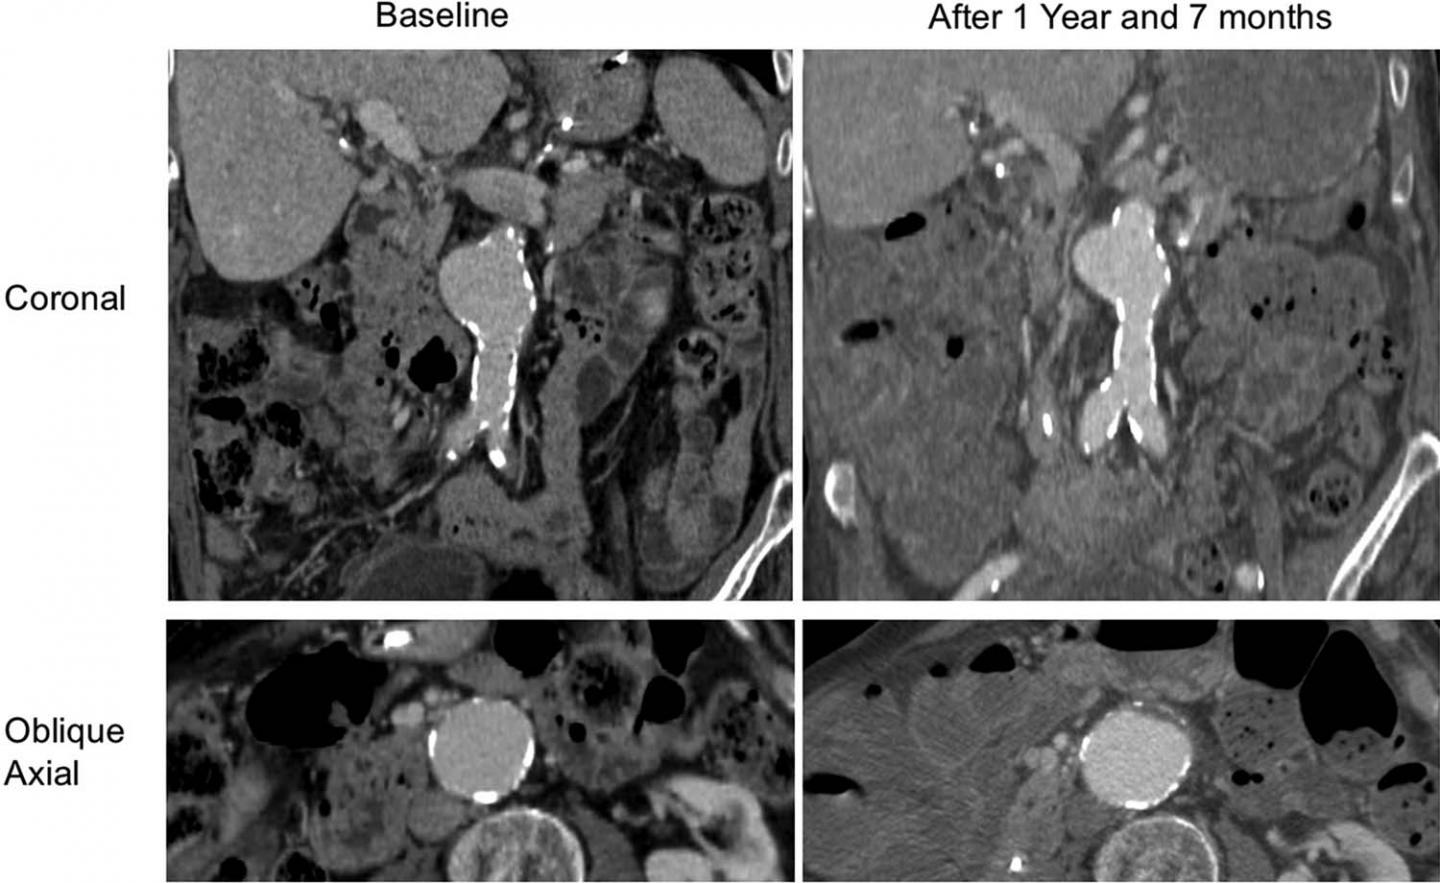

Dr. Zhu and colleagues focused their study on the intraluminal thrombus, a blood clot on the wall of the aorta at the location of the aneurysm. Intraluminal thrombi are present in the majority of aneurysms close to the repair threshold of 5.5 cm, and in a considerable number of smaller aneurysms. Despite their prevalence, the influence of these clots on abdominal aortic aneurysm growth and rupture risk is still not fully understood.

The researchers used high resolution cross-sectional imaging with CT or MRI to assess 225 men with abdominal aortic aneurysm. Follow-up lasted, on average, more than 3 years.

Slightly more than half of patients had an intraluminal thrombus. The aneurysms of those with intraluminal thrombus were larger at baseline and grew by a rate of 2 millimeters (mm) per year, twice as fast as the 1 mm per year growth rate in people without intraluminal thrombus.